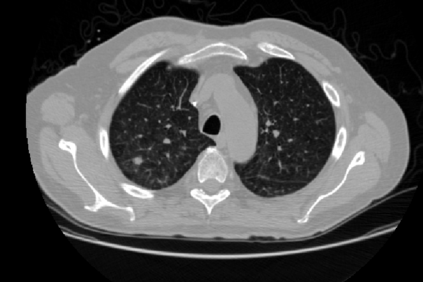

Applying artificial intelligence techniques in medical imaging is one of the most promising areas in medicine. However, most of the recent success in this area highly relies on large amounts of carefully annotated data, whereas annotating medical images is a costly process. In this paper, we propose a novel method, called FocalMix, which, to the best of our knowledge, is the first to leverage recent advances in semi-supervised learning (SSL) for 3D medical image detection. We conducted extensive experiments on two widely used datasets for lung nodule detection, LUNA16 and NLST. Results show that our proposed SSL methods can achieve a substantial improvement of up to 17.3% over state-of-the-art supervised learning approaches with 400 unlabeled CT scans.

翻译:在医学成像中应用人工智能技术是医学领域最有希望的领域之一,然而,该领域最近取得的大部分成功高度依赖于大量经过仔细注解的数据,而医疗图象的注解是一个昂贵的过程。 在本文中,我们提出了一个名为CouncleMix的新方法,据我们所知,这是利用半监督学习(SSL)的最新进展进行3D医学成像检测的第一个新方法。 我们对两种广泛使用的用于肺结核检测的数据集(LUNA16和NLST)进行了广泛的实验。 结果显示,我们提议的SSL方法可以大大改进,比最先进的监控学习方法高出17.3%,有400个未贴标签的CT扫描。